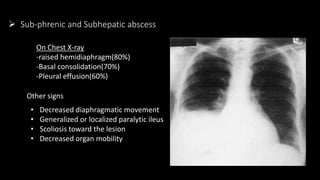

 Sub-phrenic and Subhepatic abscess

On Chest X-ray

-raised hemidiaphragm(80%)

-Basal consolidation(70%)

-Pleural effusion(60%)

Other signs

• Decreased diaphragmatic movement

• Generalized or localized paralytic ileus

• Scoliosis toward the lesion

• Decreased organ mobility